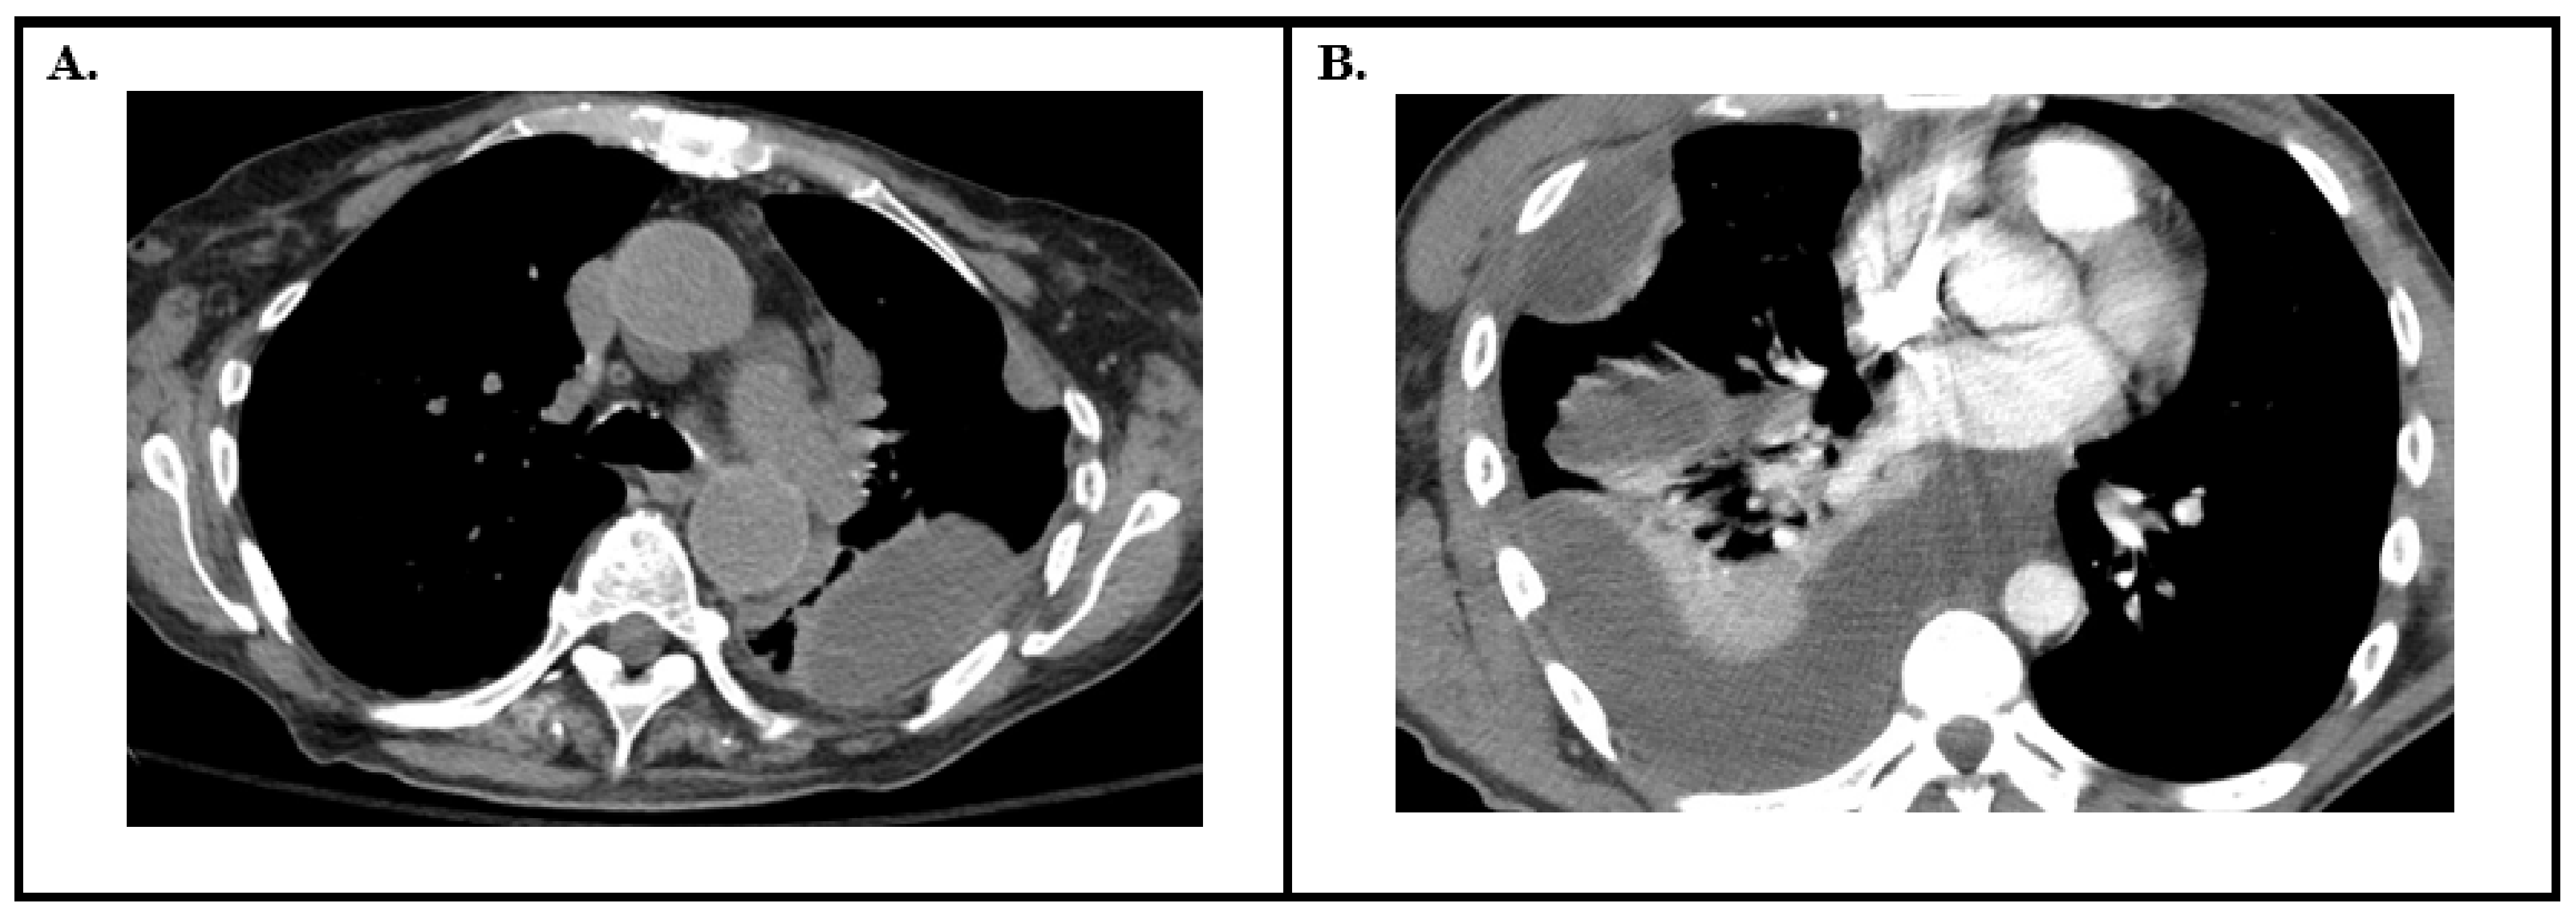

| Computed Tomography of the Chest | Minimum size to drain: >2.5 cm depth High risk findings: “Split Pleura” sign Increased attenuation of extra-pleural fat Large volume effusion Pleural thickening |